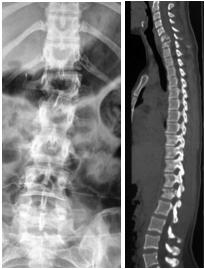

图1:21岁美国大学生,车祸致颈、腰椎多处骨折,四肢不全瘫。

FIGURE 1:A 21-year-old American college student, multiple fractures

of cervical and lumber spine in a car accident, ASIA C incomplete paralysis.

图2:手术后一周下地行走。

FIGURE 2: standing and walking one week after operation

图3:手术后9个月复查

FIGURE 3: Nine months after operation